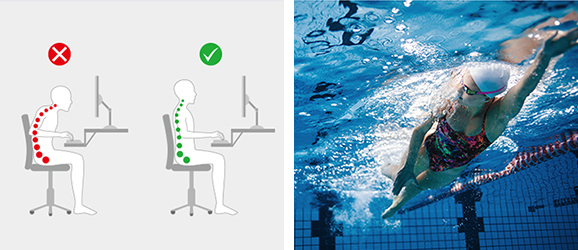

잘못된 자세는 허리에 무리를 주면서 디스크를 발생시키는 데 가장 악영향을 미치는 원인입니다. 허리를 구부린 자세, 다리를 꼬는 자세는 삼가고 의자에 엉덩이를 붙이고 허리를 곧게 펴고 앉는 것이 좋습니다.

또, 평소 자신의 자세를 꼼꼼히 살피고 바로잡아 허리에 무리를 줄이고 평소 가벼운 걷기, 수영, 근력운동을 통해 척추를 강화시켜야 합니다.